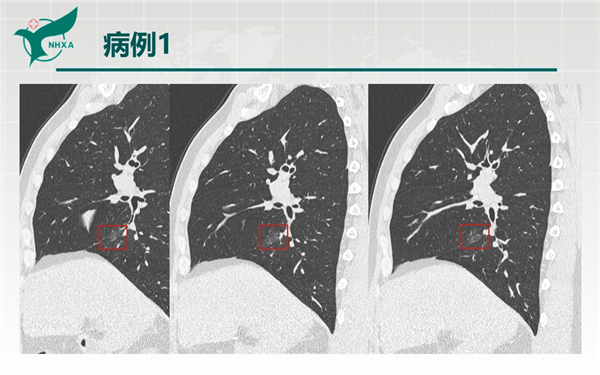

【病例分享】新型冠狀病毒肺炎3例(西安市第九醫(yī)院)

幻燈片2.jpg